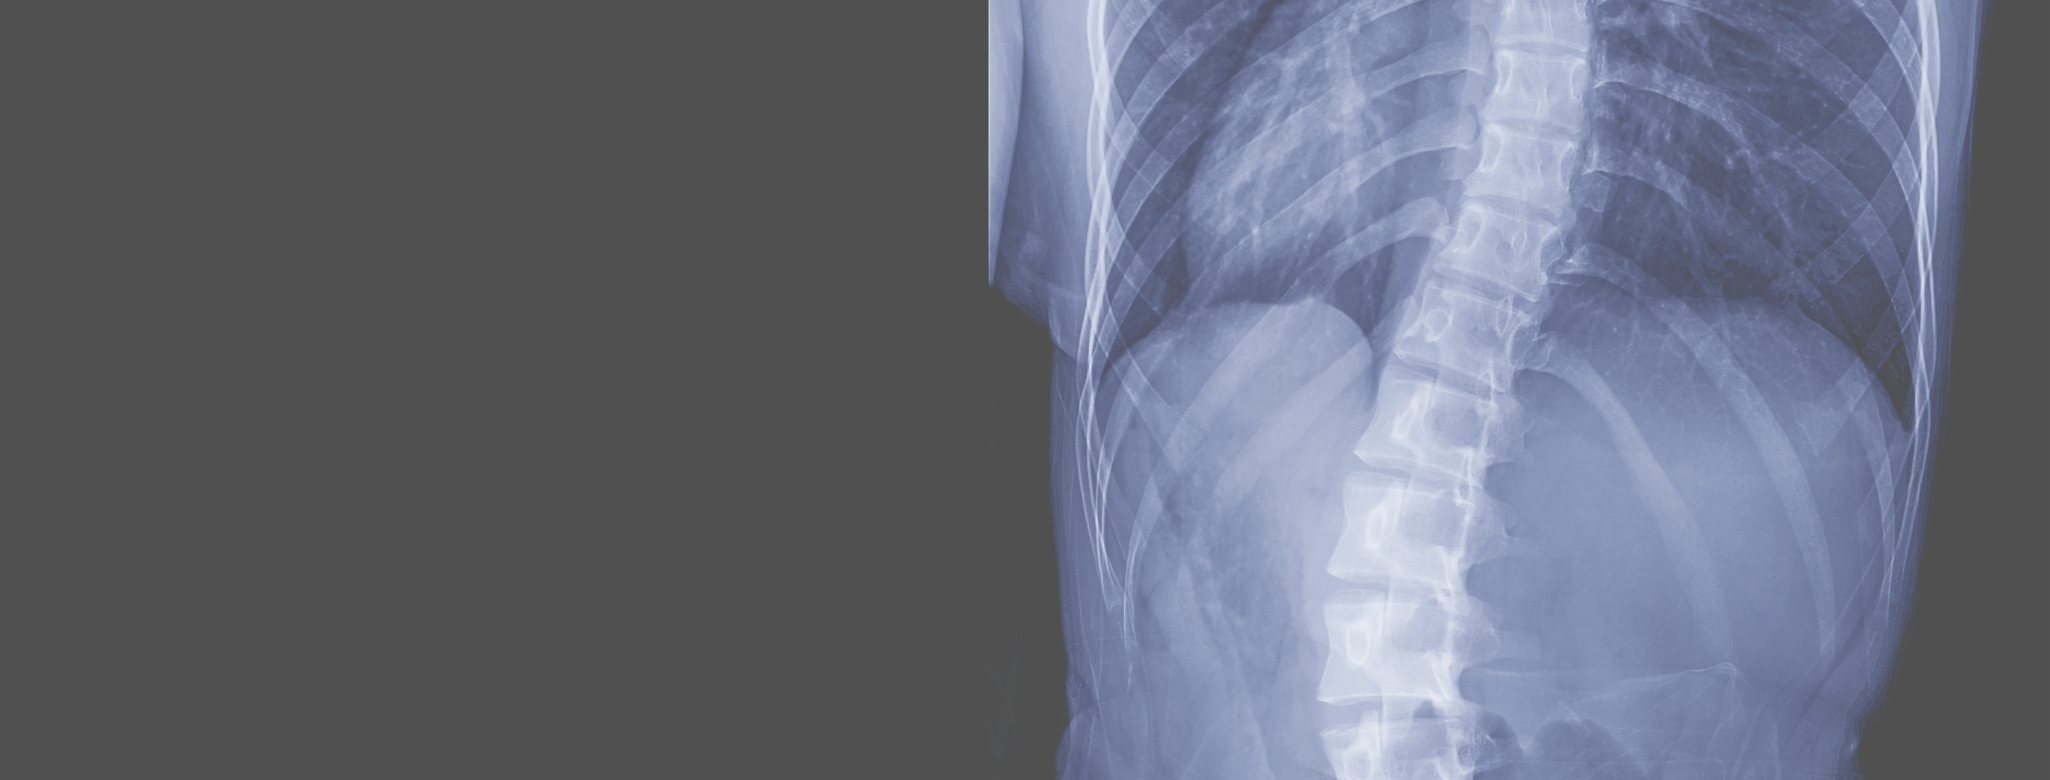

Scoliosis Screening & Treatment in Forked River Monmouth Pain Scoliosis Heavy Backpack    although there are no studies that prove backpacks can cause scoliosis, heavy backpacks worn for extended periods. What causes scoliosis and can it be prevented? Heavy backpacks can be related to back.   that’s because the development of a curved spine or adolescent idiopathic scoliosis (ais) isn’t caused by heavy bags and poor posture, according to a 2020 study. Scoliosis Heavy Backpack.